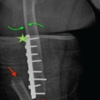

An 80-year-old female had been treated with a cemented HHA (AMIStem-C, Medacta, Castel San Pietro, Switzerland) for a low-energy femoral neck fracture (Fig. 1a). Two years later, the now 82-year-old patient tripped and fell again, suffering a PPF of the femur (Figs. 1b and 2).

Figure 1: Conventional anteroposterior radiographs of the left hip, respectively, the left fe-mur of the patient described. In (a) after cemented hemiarthroplasty, performed due to a femoral neck fracture, at an age of 80 years. In (b) periprosthetic spiral fracture of the fem-oral diaphysis, 2 years postoperatively, following a low-energy fall. In (c) after internal fix-ation of the femur. The fracture was first reduced with a cerclage (arrow), then a lateral neu-tralization plate was applied, fixated proximally with further cerclages and distally with screws. In (d) follow-up 4 months after internal fixation. Note that no callus formation is visible, indicative of absolute stability. In (e) follow-up 4 years after internal fixation. Note the atrophy of the cortical bone, both medially and laterally, but particularly under the plate (arrows). There were no signs of loosening of the stem, nor of the cement mantle. The yel-low line marks the level of the cross-section from Figs. 4 and 5.

As the treating team considered the stem to be stable, with a fracture evaluated as being located distally to the area of fixation (Unified Classification System [UCS] Type C) [17], plate fixation was chosen. Open reduction and internal fixation of the fracture was performed through a subvastus approach, with reduction and fixation by a cable cerclage (Cable System 1.7 mm, DePuy Synthes, Zuchwil, Switzerland) and application of a lateral neutralization plate (non-contact bridging [NCB] Periprosthetic Femur Plate System 18 hole, Zimmer Biomet, Zug, Switzerland), fixated distally with screws and along the level of the stem with further cable cerclages (Cable System 1.7 mm). Postoperatively, the patient was mobilized in a wheelchair, as full weight-bearing was not recommended and as it was not possible to implement partial weight-bearing. Wound healing was uneventful. The radiological follow-up after 8 weeks showed intact material without evidence of loosening (Fig. 1c). Mobilization under full weight-bearing with support by physical therapy was then attempted. Four months postoperatively, the radiological follow-up showed a general atrophy of the cortical bone, which was accentuated at the lateral cortex, underneath the plate (Fig. 1d). Mobilization was hampered due to thigh pain, which had been interpreted to be caused by muscle atrophy. Thus, further physical therapy was recommended. As the impaired mobility caused difficulties attending consultation at the hospital, no further follow-up visits were planned. Due to increasing thigh pain, the patient was readdressed for evaluation by her general practitioner 4 years after the operative treatment of the PPF. Not having been mobilized outside a wheelchair in the meantime, the patient showed bilateral hip and knee flexion contractures. Consequently, she was unable to stand, disregarding the issue of thigh pain. Radiologically, there was now pronounced atrophy of the cortical bone of the femur, particularly of the lateral cortex under the plate (Fig. 1e). An infection was considered unlikely, as there was no pain at rest, as the soft tissues were inconspicuous, as the fracture had healed, and as there were no general symptoms. A single-photon emission computed tomography (CT) showed avascular areas of cortical bone underneath the plate (Fig. 3). The CT better illustrated a general atrophy of the femur with thinning of the bone cortex in comparison to the contralateral femur (Fig. 4 and 5). There was, however, no sign of loosening of the stem. Considering comorbidities, very limited potential for recovery, and the patients’ desire for no more surgery, the option of a revision was rejected, accepting the present situation. The patient died 7 months later.